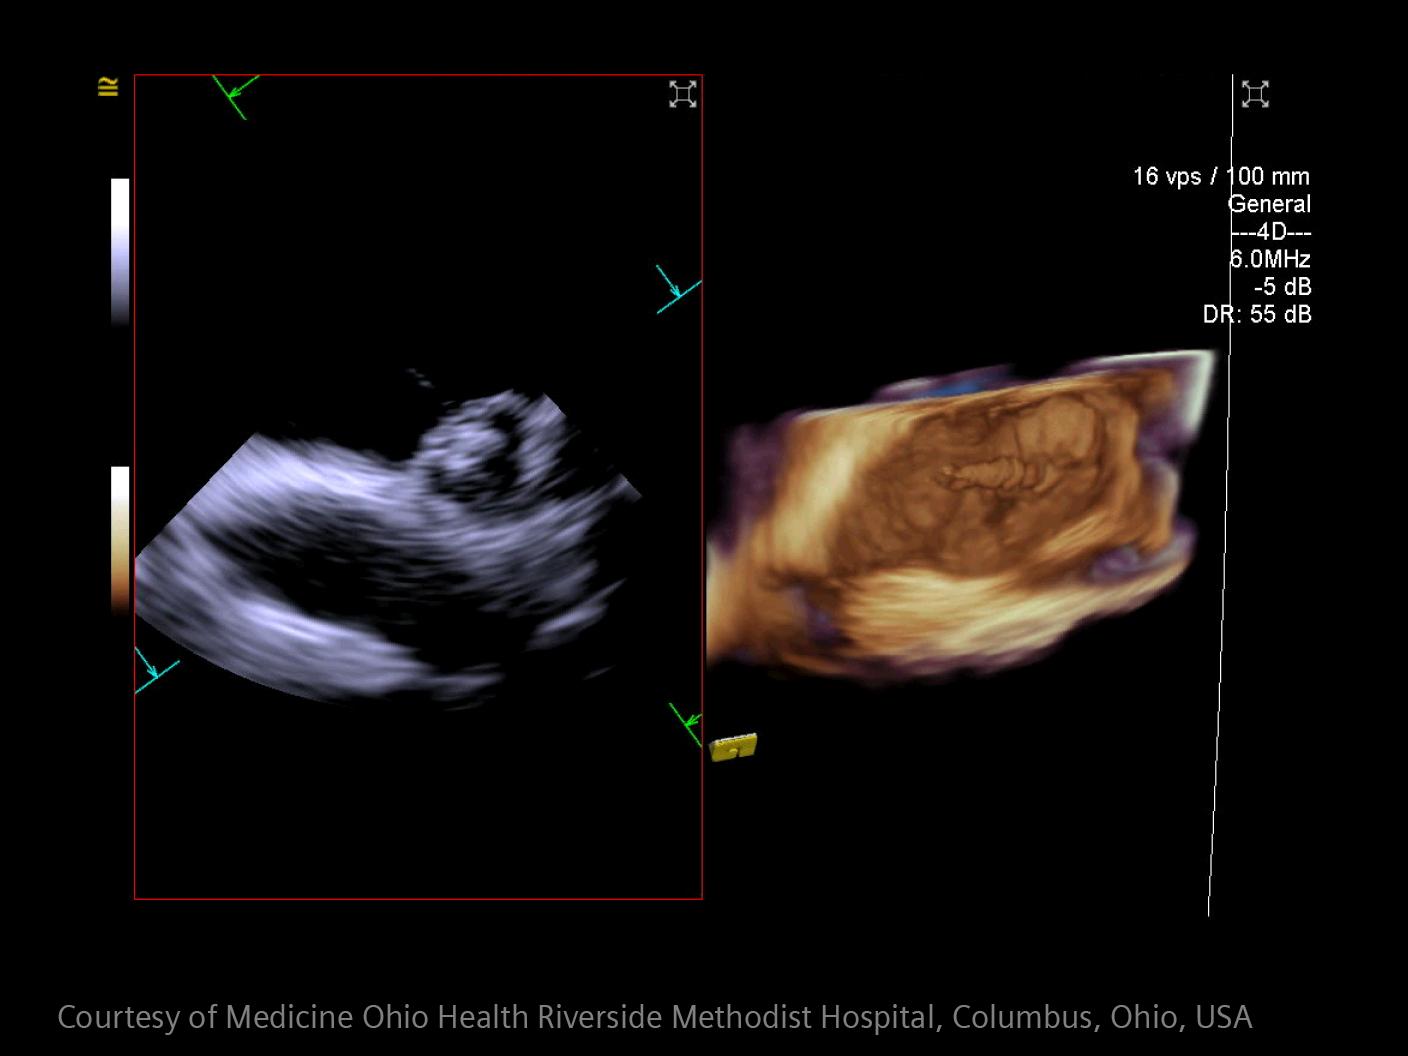

How advanced imaging and AI transform stroke workflow

In stroke care, time is brain. Rapid and accurate imaging is crucial to assess the extent of brain injury and guide immediate treatment. Angiography, MRI, CT, ultrasound, and lab diagnostics are essential tools in identifying stroke type, location, and severity. Advances in imaging technology now allow for even faster acquisition, improved resolution, and enhanced visualization of brain tissue and blood vessels. Innovations such as perfusion imaging, real-time vascular mapping, and AI-assisted diagnostics are transforming stroke workflows and enabling precise, timely interventions.